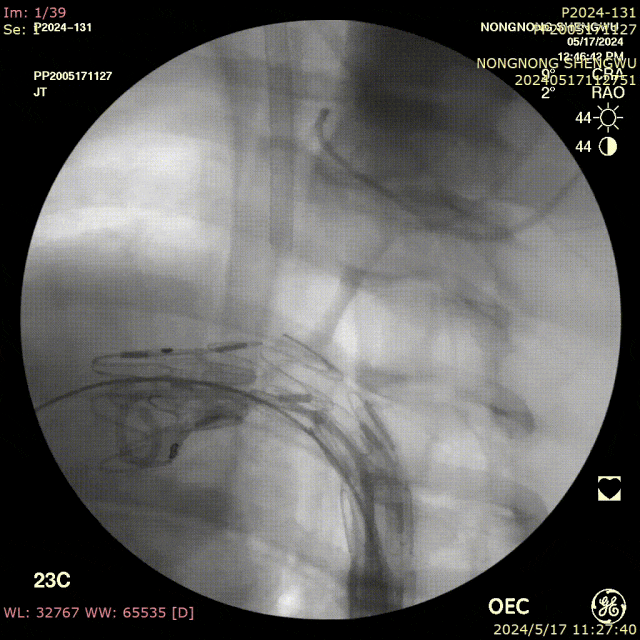

我们在两头35kg巴马公猪中完成动物实验:

成功实现弓上分支的快速、准确原位开窗;

破膜过程流畅,无分支或主动脉损伤;

取出标本可见圆形破口、支架贴合良好,证实技术可行性。

动物实验

巴马公猪35kg